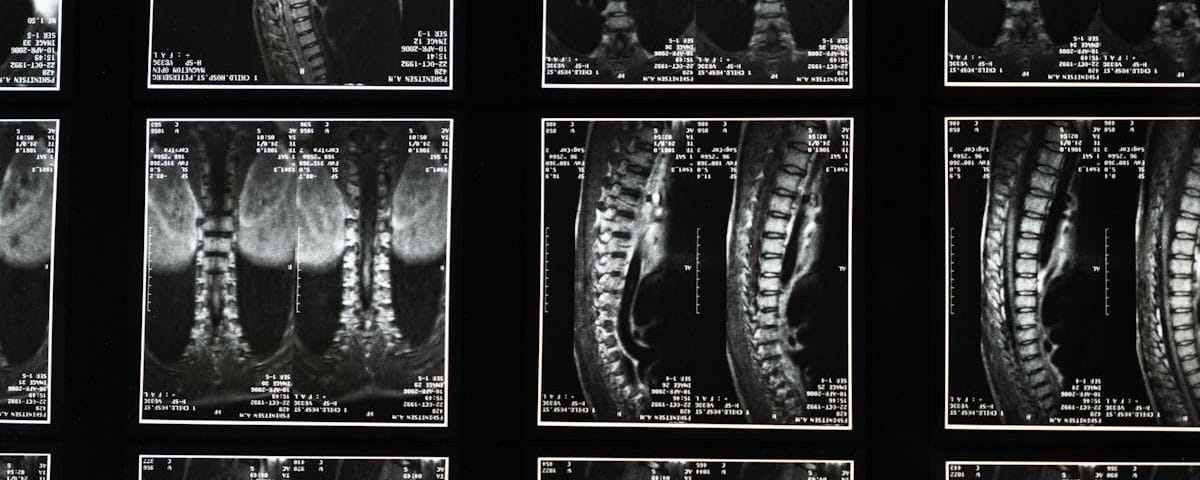

La décompression spinale est une thérapie non invasive qui traite divers troubles de la colonne vertébrale tels que les hernies discales, les douleurs lombaires ou la sciatique. En utilisant un appareil spécialisé, des forces de traction sont appliquées, permettant ainsi aux disques intervertébraux de retrouver leur position normale. Cette méthode aide à réduire la douleur et à améliorer la flexibilité et la mobilité de la colonne vertébrale.

La décompression spinale est une méthode non invasive qui consiste à appliquer des forces de traction sur la colonne vertébrale pour créer un espace entre les vertèbres. En réduisant la compression exercée sur les disques intervertébraux, cette technique aide à soulager la pression sur les nerfs et à réduire les douleurs. Avec un équipement spécialisé, la décompression peut aussi favoriser l’hydratation et la respiration des disques, favorisant ainsi leur guérison.